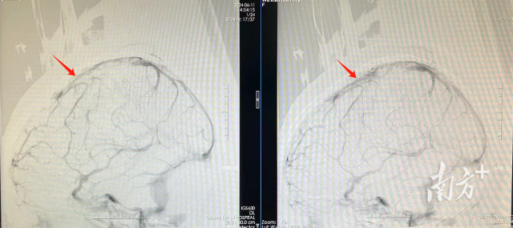

患者取栓前后对比照:取栓前静脉窦显影不佳(左),取栓后静脉窦显影好转(右)。

广东三九脑科医院神经外十科及神经血管介入科急诊为患者进行全脑血管造影。结果显示,患者的上矢状窦、右侧横窦等颅内大静脉完全堵塞,证实是大静脉窦血栓。

随后,医生紧急将堵塞在患者静脉窦内的栓子取出,再应用抗凝血药物进一步稳定病情。“静脉血管通畅后,颅压下降,患者颅内的血块有望自行吸收,无需再进行开颅手术。”该院神经外十科主治医师冯桂栗介绍道。